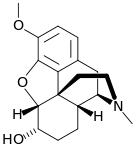

Morphinones and morphols

- 14-Cinnamoyloxycodeinone

- 14-Ethoxymetopon

- 14-Methoxymetopon

- 14-Phenylpropoxymetopon

- 3-Acetyloxymorphone

- 3,14-Diacetyloxymorphone

- 7-Spiroindanyloxymorphone

- 8,14-Dihydroxydihydromorphinone

- Acetylcodone

- Acetylmorphone

- α-hydrocodol (=dihydrocodeine, )

- Benzhydrocodone

- Bromoisopropropyldihydromorphinone cas?

- Codeinone

- Codoxime

- Conorfone (codorphone)

- IBNtxA

- Thebacon (acetyldihydrocodeinone, dihydrocodeinone enol acetate)

- Hydrocodone

- Hydromorphone

- Hydroxycodeine

- Metopon (=methyldihydromorphinone)

- Morphenol

- Morphinone

- Morphol

- N-Phenethyl-14-ethoxymetopon

- Noroxymorphone

- Oxycodone

- Oxymorphol

- Oxymorphone

- Pentamorphone

- Semorphone

Structures

| Morphinones and morphols | ||||